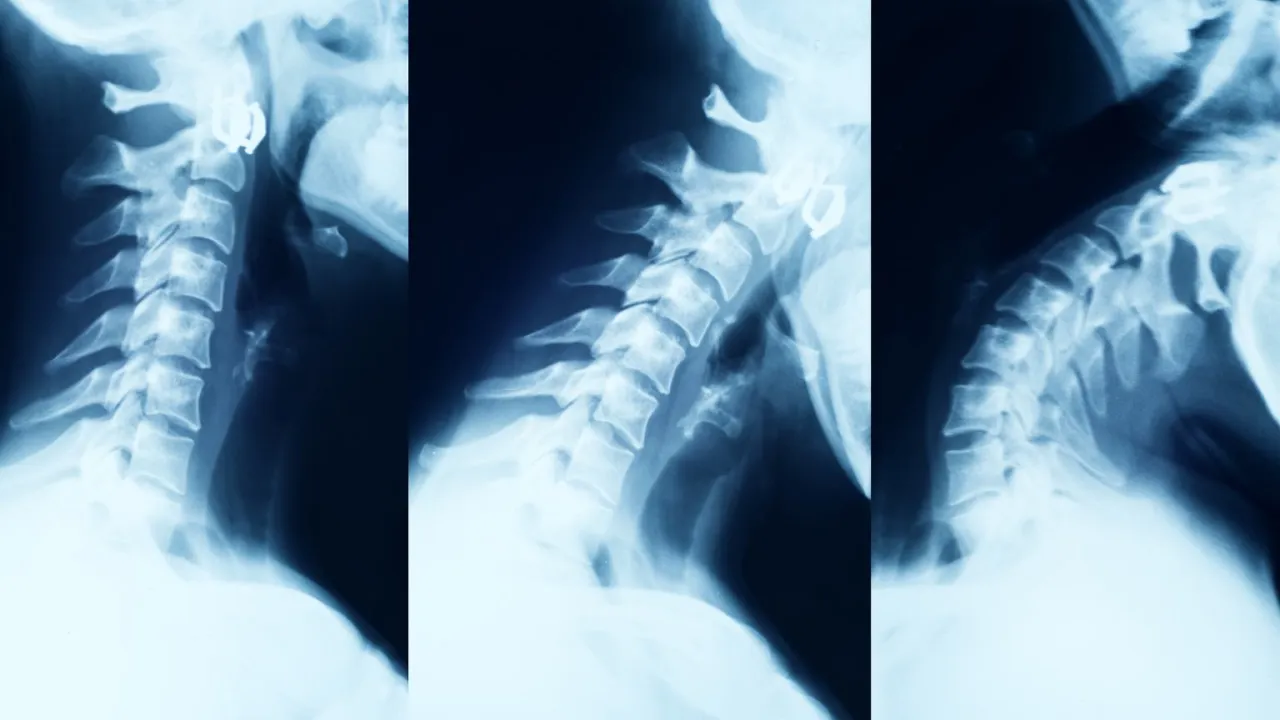

Odcinek szyjny: Gdy drętwieją ręce, a w głowie się kręci

Zmiany zwyrodnieniowe w odcinku szyjnym kręgosłupa są bardzo często spotykane i mogą dawać niezwykle uciążliwe objawy. Kiedy dochodzi do ucisku na korzenie nerwowe wychodzące z szyi, pacjenci często doświadczają rwy barkowej. Jest to ból, który promieniuje od karku, przez bark, ramię, przedramię, aż do dłoni i palców. To jednak nie wszystko. Nierzadko pojawiają się również drętwienie i mrowienie rąk lub palców, co jest sygnałem zaburzeń czucia. Może dojść także do osłabienia siły mięśniowej kończyn górnych, co w praktyce objawia się trudnościami z chwytaniem przedmiotów, zapinaniem guzików czy utrzymywaniem rzeczy w dłoniach. To niezwykle frustrujące, gdy proste, codzienne czynności stają się wyzwaniem.

Po badaniu klinicznym, lekarz zazwyczaj zleca badania obrazowe. Rezonans magnetyczny (MRI) jest obecnie najdokładniejszym i najczęściej stosowanym badaniem do diagnozowania problemów kręgosłupa, zwłaszcza gdy podejrzewa się ucisk na struktury nerwowe. MRI pozwala na szczegółowe zobrazowanie krążków międzykręgowych, rdzenia kręgowego, korzeni nerwowych, a także ewentualnych przepuklin, zwężeń kanału kręgowego czy zmian zapalnych. Dzięki niemu możemy dosłownie "zajrzeć do wnętrza" kręgosłupa i precyzyjnie zlokalizować źródło problemu.